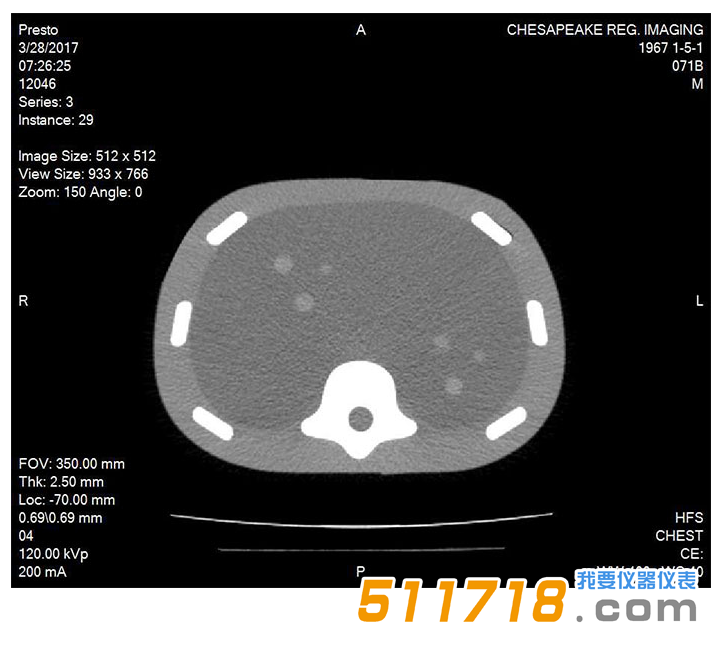

071B CT圖像

CIRS 071B腹部模體,圖像引導(dǎo)腹部活組織檢查模體包含12個(gè)病灶,直徑5-12mm,以三個(gè)一組的方式放置在體模內(nèi)的一致位置。它還包括模擬脊柱和肋骨,以及脊柱內(nèi)的“H”標(biāo)記,以幫助確定CT圖像中的頭側(cè)。

在超聲,CT和MRI下可見(jiàn)病變和脊柱。固體聚合物凝膠背景是消聲的,穿刺時(shí)不會(huì)泄漏。*

| 其他 | CT可見(jiàn)“H”標(biāo)記表示頭/腳方向(由鉛制成 - 與MRI兼容) |